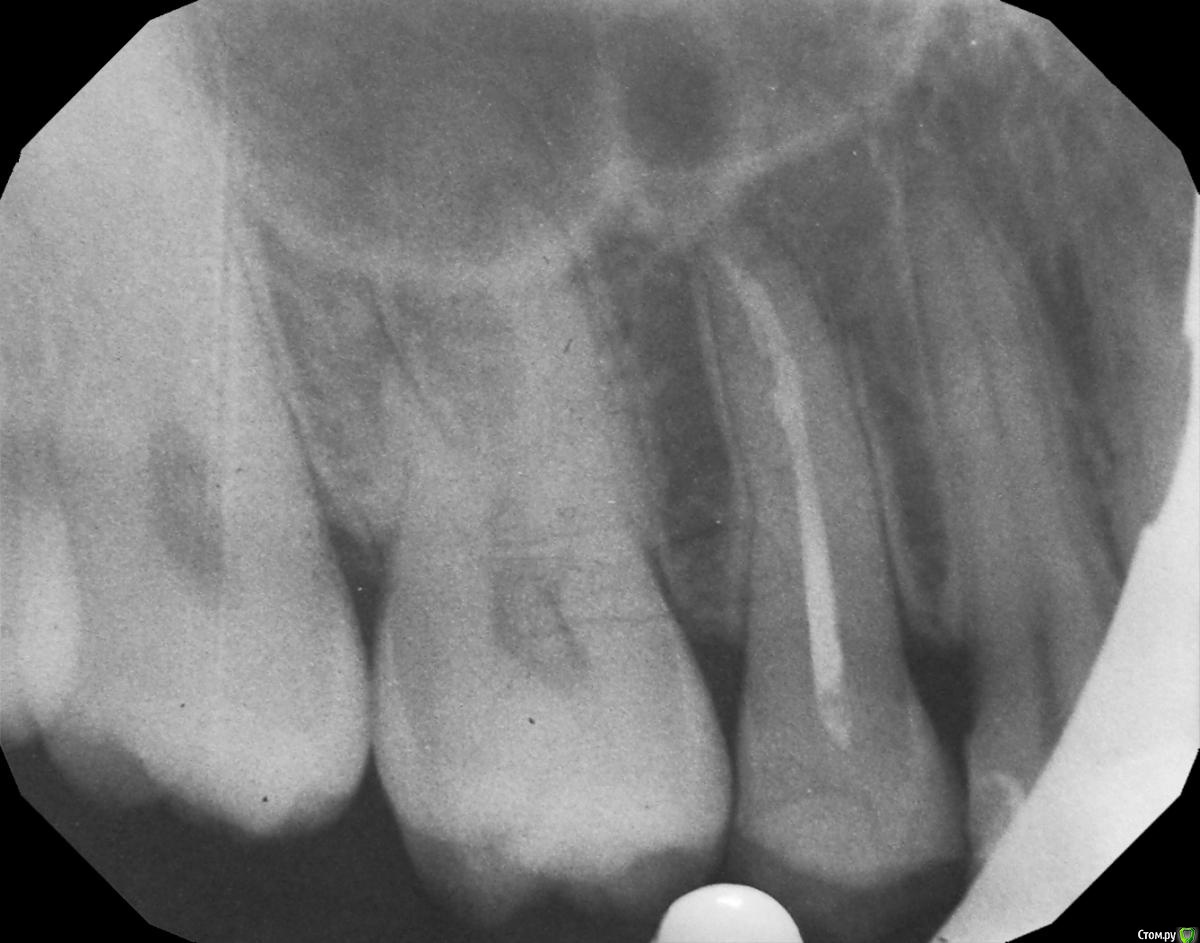

hichi Опубликовано 25 сентября, 2015 Автор Поделиться Опубликовано 25 сентября, 2015 (изменено) покажите все снимки начиная с первого Гарриевич сказал(а) 22 Сен 2015 - 00:35: покажите все снимки начиная с первого + 1 пожалуйста первичное эндо когда заболел от горячего искали доп. анатомию кальций с ложным ходом есть только один снимок, который в самом первом сообщенииесть еще один через 3 мес после лечения но он не совсем удачно сделан, думаю ничем вам не поможет Изменено 25 сентября, 2015 пользователем hichi Ссылка на комментарий

red_butler Опубликовано 25 сентября, 2015 Поделиться Опубликовано 25 сентября, 2015 Выглядит все очень прилично. Ссылка на комментарий